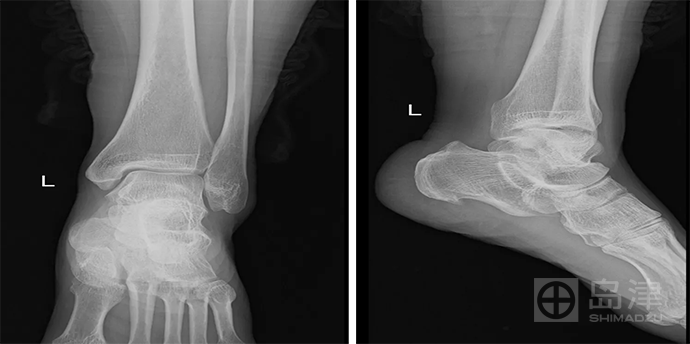

45岁 女性 左踝扭伤

左踝正侧位X线片无明显骨折线,骨折间接征象:软组织肿胀亦不明显。

查体:局部压痛明显。

DTS发现骨折,与 CT对比结果一致。

隐匿性骨折 DR无法发现

左外踝隐匿性骨折

DTS可发现平片无法发现的骨折

图像来源:西安市第九医院